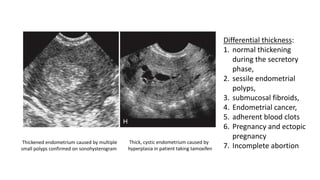

• Ultrasound Findings

-Endometrial hyperplasia is considered when the endometrium

exceeds 10 mm in thickness, especially in menopausal patients

-In postmenopausal women, 5mm thickness is significant.

-May also cause asymmetric thickening with surface irregularity, an

appearance that is suspicious for carcinoma.

Thickened endometrium caused by multiple

small polyps confirmed on sonohysterogram

Thick, cystic endometrium caused by

hyperplasia in patient taking tamoxifen

Differential thickness:

1. normal thickening

during the secretory

phase,

2. sessile endometrial

polyps,

3. submucosal fibroids,

4. Endometrial cancer,

5. adherent blood clots

6. Pregnancy and ectopic

pregnancy

7. Incomplete abortion

• Endometrial hyperplasia has a nonspecific appearance so any focal

abnormality should lead to biopsy if there is clinical suspicion for

malignancy.